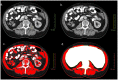

Patient and methods: 174 patients with primary operable colorectal cancer who underwent resection with curative intent (2003-2010). Image analysis of CT scans was used to measure total fat index (cm(2)/m(2)), subcutaneous fat index (cm(2)/m(2)), visceral fat index (cm(2)/m(2)) and skeletal muscle index (cm(2)/m(2)). Systemic inflammatory response was measured by serum white cell count (WCC), neutrophil:lymphocyte ratio (NLR) and the Glasgow Prognostic Score (mGPS).